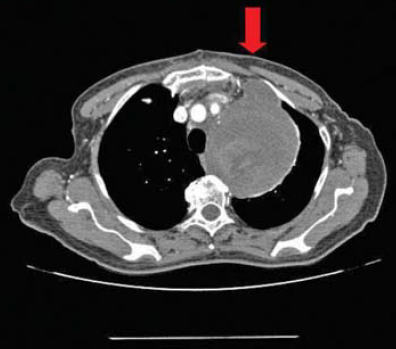

3. ábra.

PAU a proximalis aortaív hátsó felszínén.

A 18 betegből 6 nő és 12 férfi volt. Az életkor 24 és 75 év között váltakozott, a medián érték 65,7 év volt. A penetráló ulcus 10 esetben tünetmentes volt, véletlenszerűen került felfedezésre rutin mellkas röntgenvizsgálat során. 8 beteg mellkasi, 3 háti, 2 felhasi fájdalom, 3 lázas állapot miatt került részletes vizsgálatra. A kórkép pontos diagnosisának felállításában minden esetben CT angiographiát (CTA) és öt betegnél digitalis subtractiós angiographiát (DSA) is végeztünk a mellékágak morfologiai viszonyainak pontosítására (1. Táblázat).